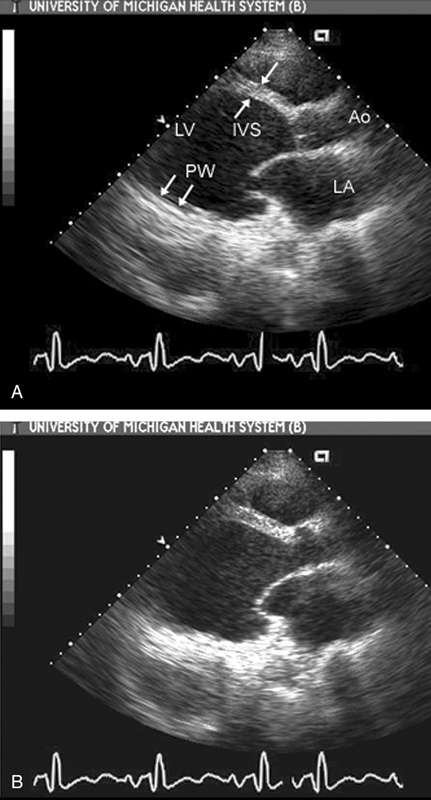

فحوصات تشخيصية لبعض امراض القلب والشرايين التاجية